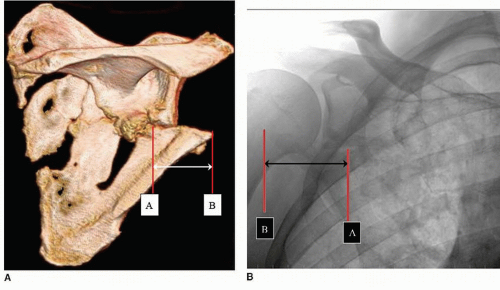

صورة كسر الكتف

• الأشعة السينية: تساعد الأشعة السينية في توضيح مدى الكسر ونوعه وموقعه.